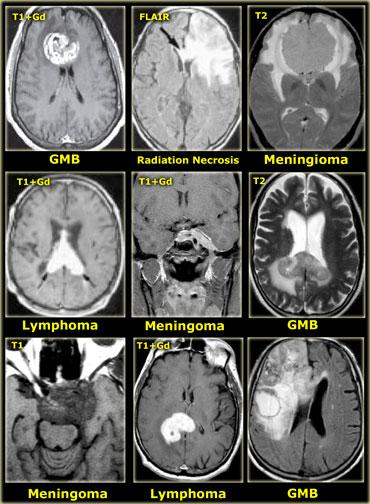

U nguyên bào đa dạng (GBM) với ngấm thuốc không đồng nhất và thành phần nang với ngấm thuốc dạng vòng

Ngấm thuốc không đồng nhất (dạng đốm) có thể thấy trong:

- Di căn não

- U ít nhánh (Oligodendroglioma)

- U nguyên bào đa dạng (Glioblastoma multiforme)

- Hoại tử do xạ trị

Bên trái là ví dụ về u nguyên bào đa dạng (GBM).

Sự ngấm thuốc cho thấy đây là khối u độ cao, nhưng chỉ một phần của khối u ngấm thuốc.

Lưu ý rằng còn có một thành phần nang với ngấm thuốc dạng vòng.

Các tế bào u có thể lan rộng vượt ra ngoài vùng phù não như thấy trên ảnh FLAIR.

Điều này là do u thần kinh đệm phát triển thâm nhiễm vào nhu mô não bình thường – ban đầu không có bất kỳ thay đổi tín hiệu MRI nào.

Ngấm thuốc dạng vòng

Ngấm thuốc dạng vòng được thấy trong di căn não và u thần kinh đệm độ cao.

Nó cũng được thấy trong các tổn thương không phải u như áp xe, một số mảng xơ cứng rải rác (MS) và đôi khi trong khối máu tụ cũ.

Bên trái là ba tổn thương ngấm thuốc dạng vòng khác nhau.